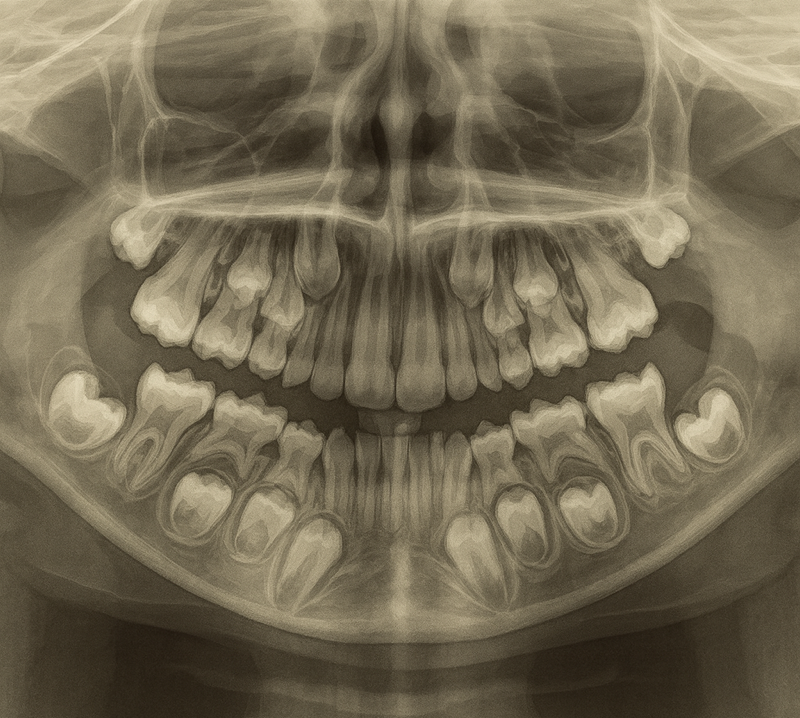

영구치가 나오는 시기를 정리하는 그림입니다. (출처: https://brookhavenchildrensdentistry.com/)

아이 치아는 다음 순서로 자랍니다:

- 앞니 (7~9세)

- 작은어금니(10~12세)

- 두 번째 큰어금니(12~13세)

그리고 이 모든 변화가 일어나는 시기를

혼합치열기라고 부릅니다.